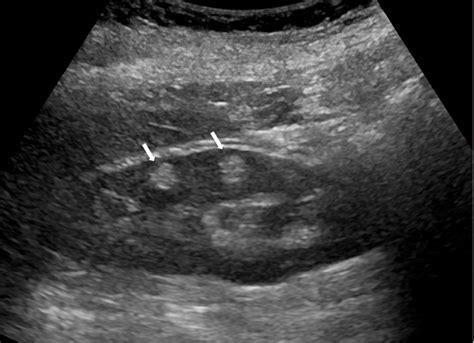

• Ultrasound: Often used as an initial screening tool; the tumors typically appear bright (hyperechoic) due to their high fat content.